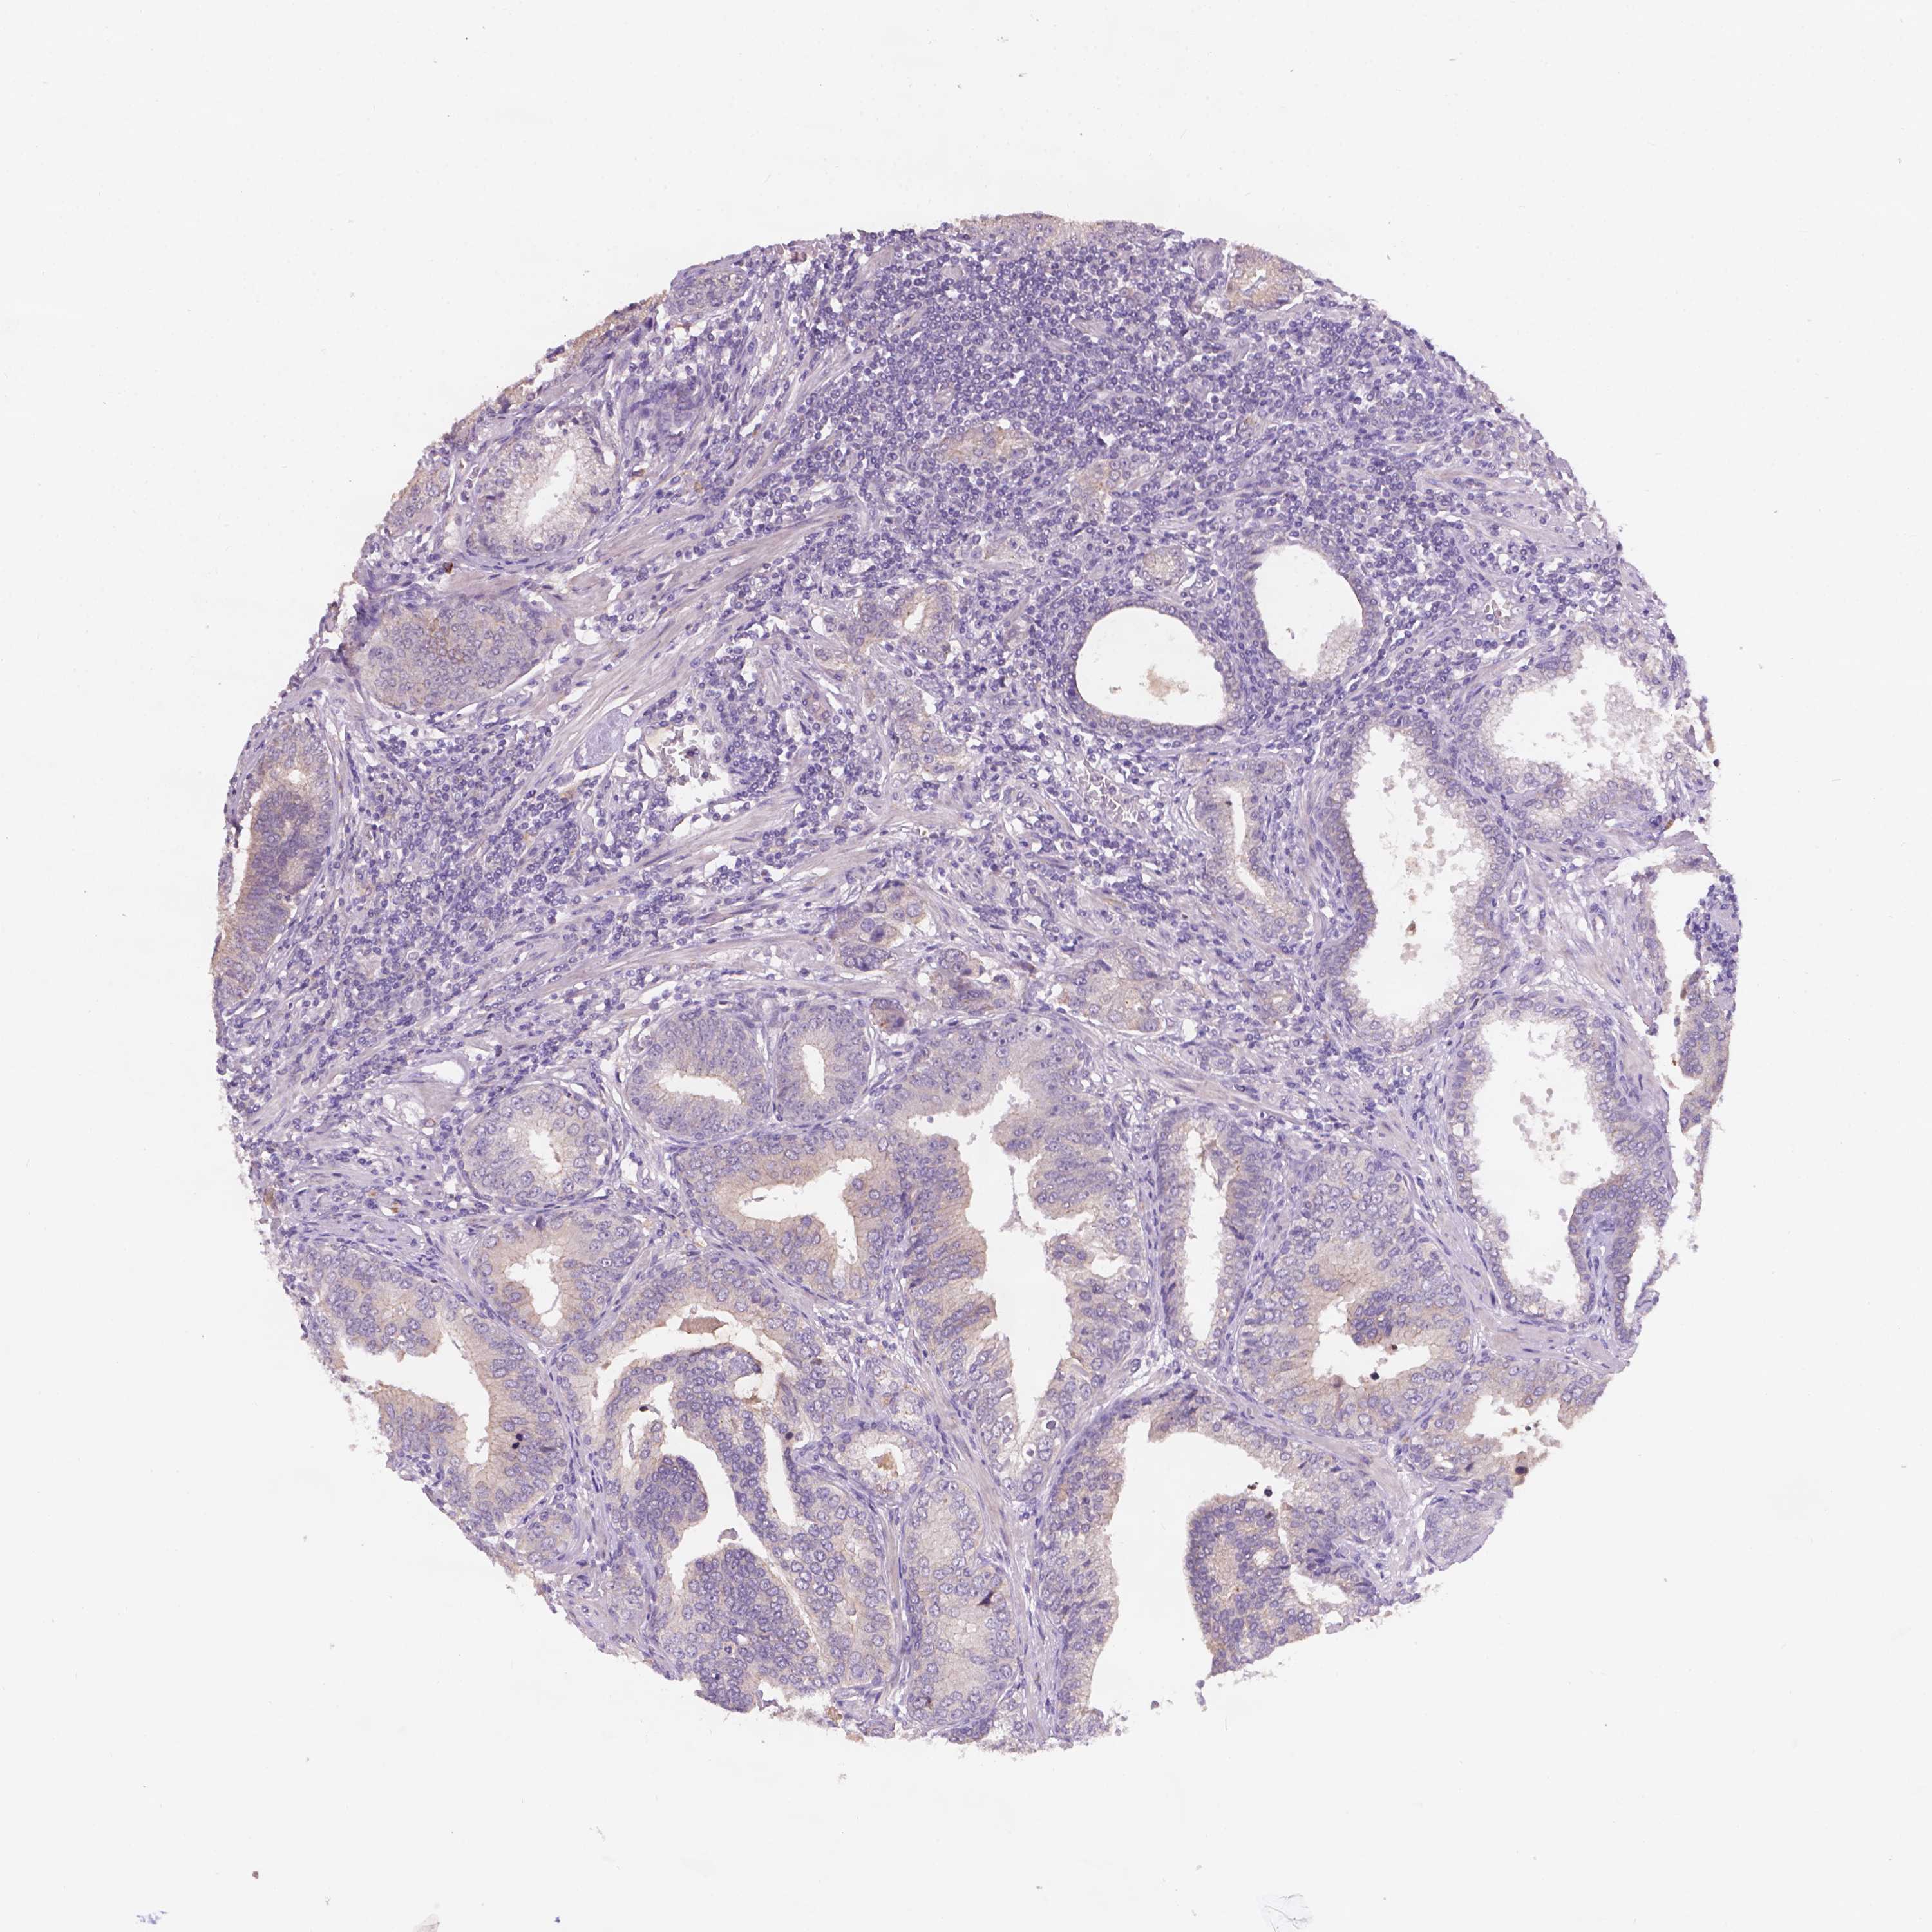

PROSTATE CANCER - Protein expressioni

A mouse-over function shows sample information and annotation data. Click on an image to view it in a full screen mode. Samples can be filtered based on level of antibody staining by selecting one or several of the following categories: high, medium, low and not detected. The assay and annotation is described here.

Note that samples used for immunohistochemistry by the Human Protein Atlas do not correspond to samples in the TCGA dataset.

Antibody stainingi

Antibody staining in the annotated cell types in the current human tissue is reported as not detected, low, medium, or high, based on conventional immunohistochemistry profiling in selected tissues. This score is based on the combination of the staining intensity and fraction of stained cells.

Each image is clickable and will lead to virtual microscopy that enables deeper exploration of all samples and also displays staining intensity scores, fraction scores and subcellular localization as well as patient and tissue information for each sample.

Antibody HPA068429

Staining

High

Medium

Low

Not detected

Intensity

Strong

Moderate

Weak

Negative

Quantity

>75%

75%-25%

<25%

None

Location

Nuclear

Cytoplasmic/membranous

Cytoplasmic/membranous,nuclear

Adenocarcinoma, High grade

Adenocarcinoma, NOS

Adenocarcinoma, Low grade